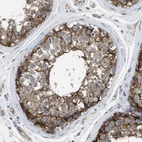

Immunohistochemical staining of human Testis shows strong membranous and granular cytoplasmic positivity in cells in seminiferous ducts.